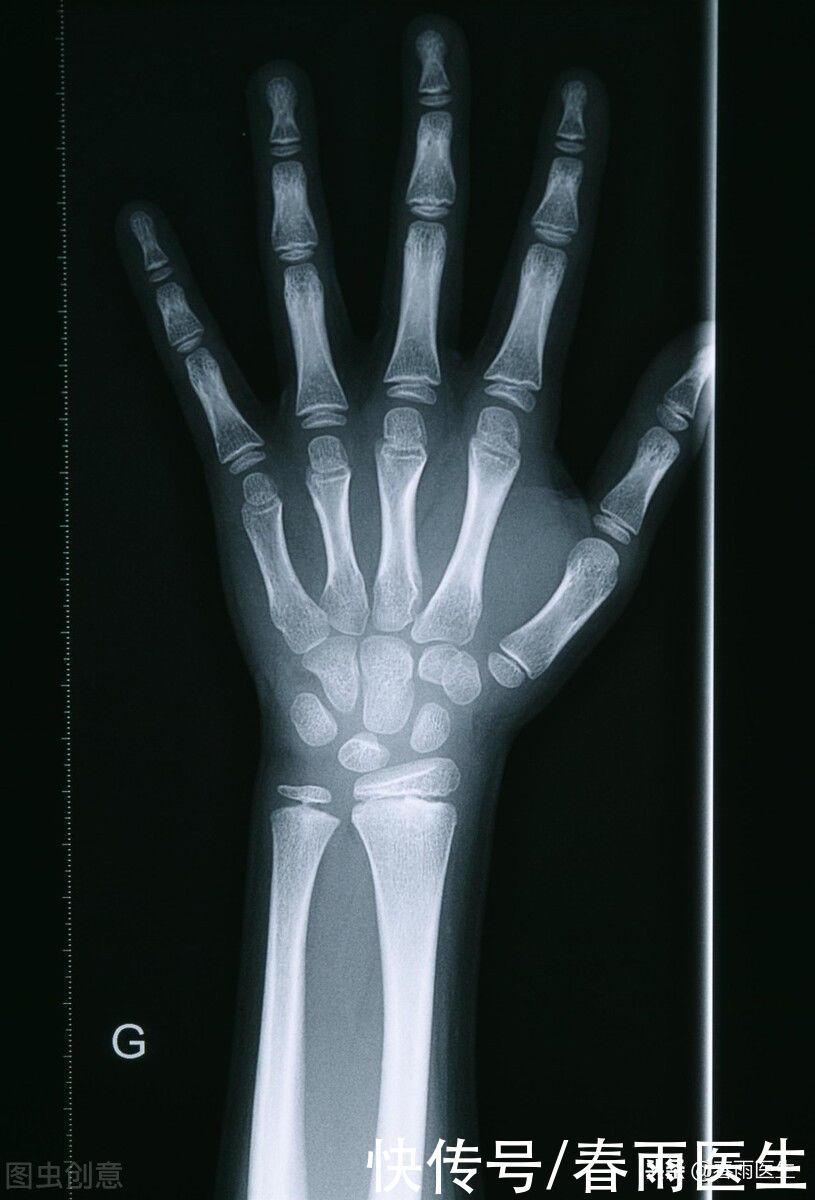

测骨龄

文章插图

测骨龄需要借助X片,根据拍片的结果可以判断骨骼的年龄,正常的孩子,骨龄与自己的年龄同步,但是矮小症的孩子,骨龄会出现异常。不少家长会担心X片的辐射会对孩子健康造成影响,不过单次测骨龄的X线辐射量符合国家安全标准,对孩子造成的辐射量是比较小的。